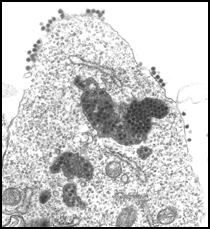

Vírus da dengue (Ortrud Monika

Barth/ Departamento de Virologia/IOC/Fiocruz)